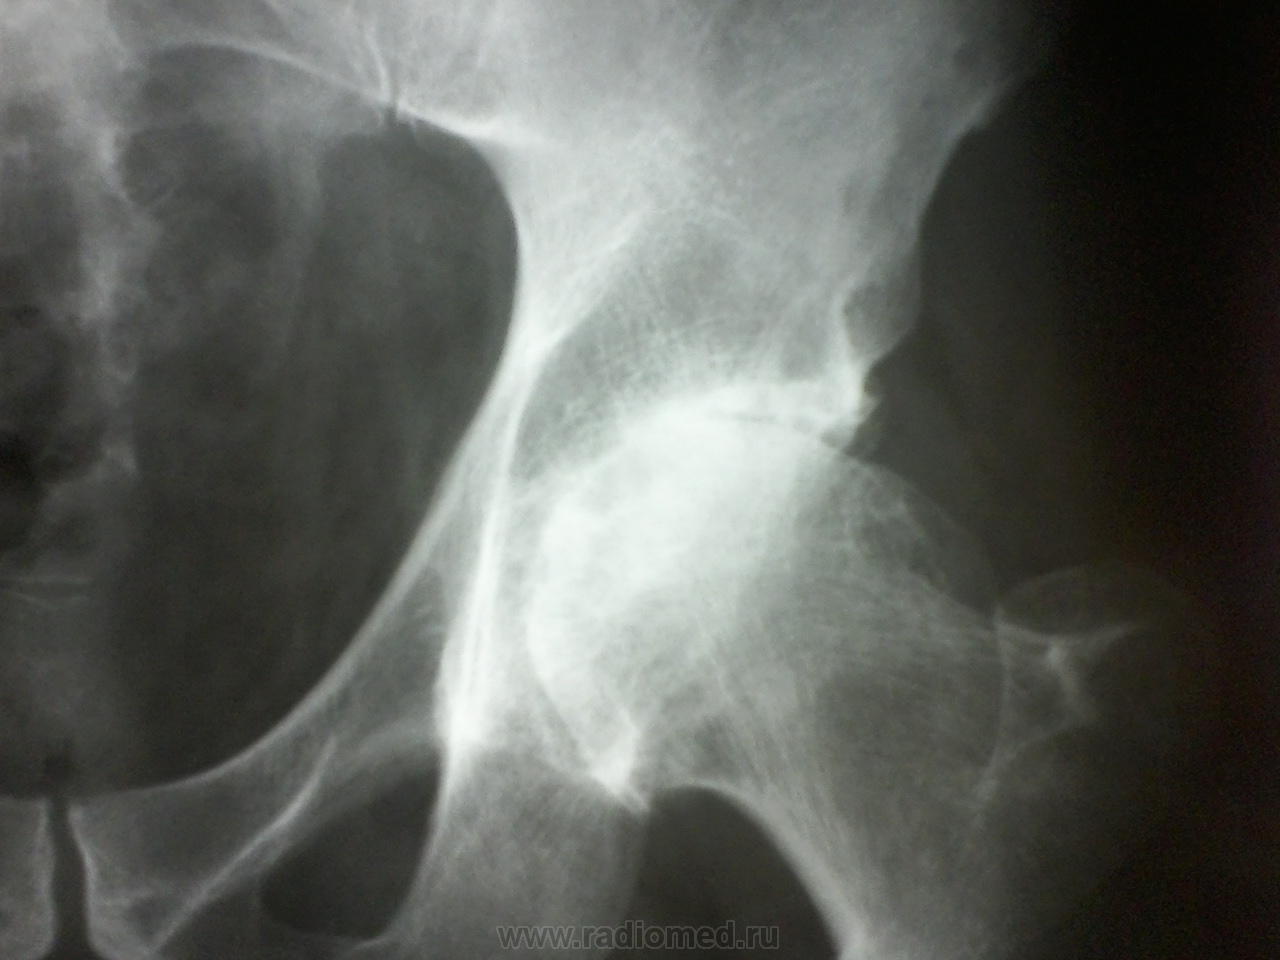

Сегодня-таки сделала томографию, может быть добавите что-то к мнениям, если можно ?

Приложения:

foto-0065.jpgfoto-0066.jpgfoto-0070.jpgfoto-0071.jpg

С удовольствием бы добавил, но лучше Валентина Львовича Никто в томограммах не понимает.)

Спасибо всем, написала деф.артроз, асептический некроз не поставила